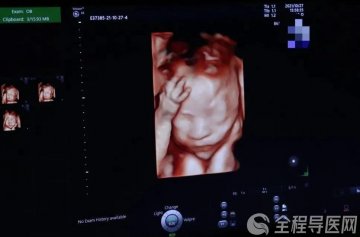

课程伊始,张平护士长借助大屏幕,向准妈妈们介绍“第一产程” 。从规律宫缩的开始,到宫口逐渐扩张,护士长用通俗易懂的语言,让大家对这个漫长却重要的阶段有了清晰认知,缓解了准妈妈们对未知的恐惧。

为了让准妈妈们更直观地理解,张平护士长拿出了特制的 “分娩宫口示意图” 道具。通过现场演示,准妈妈们清楚地看到宫口从 1 指到 10 指的变化过程,也明白了不同阶段自己该如何配合。护士长生动的讲解和形象的演示,让原本抽象的知识变得简单易懂。